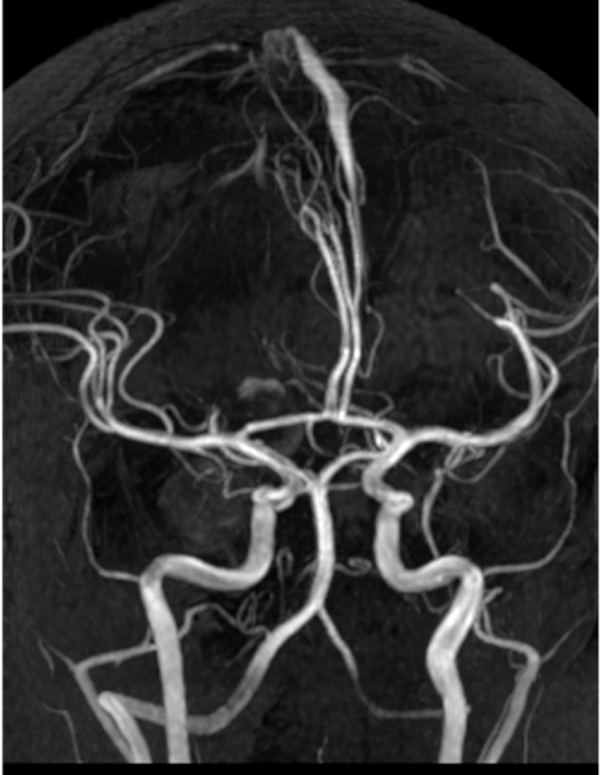

Se efectuó una craneotomía suboccipital lateral con evacuación del absceso cerebeloso. En la evolución, el paciente presentó un hematoma espontáneo secundario a la rotura de un aneurisma fusiforme del segmento P3 de la arteria cerebral posterior, confirmado por angiografía digital. El hallazgo fue interpretado como un aneurisma micótico, por lo que se realizó tratamiento endovascular. La resonancia magnética posterior a la embolización no evidenció aneurisma residual (Figuras 1 y 2).

Figura 2. AngioRM de vasos intracraneales. Control posterior a la embolización aneurismática, sin evidencia de aneurismas residuales.